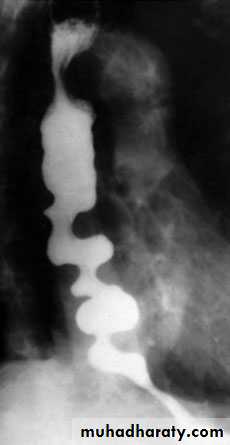

Contrast radiology:

Dilated oesophagus

Tapering stricture…bird’s beak

Absent gas bubble